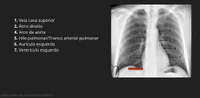

O que cada arco mediastinal representa?

1. Veia cava superior / 2. Átrio direito / 4. Arco da aorta / 5. Tronco arterial pulmonar / 6. Aurícula esquerda / 7. Ventrículo esquerdo

Veia jugular interna / 2. Átrio direito / 4. Tronco da aorta / 5. Tronco arterial pulmonar / 6. Aurícula esquerda / 7. Ventrículo esquerdo

1.Veia cava superior / 2. Átrio esquerdo / 4. Arco da aorta / 5. Veia pulmonar / 6. Aurícula esquerda / 7. Ventrículo esquerdo